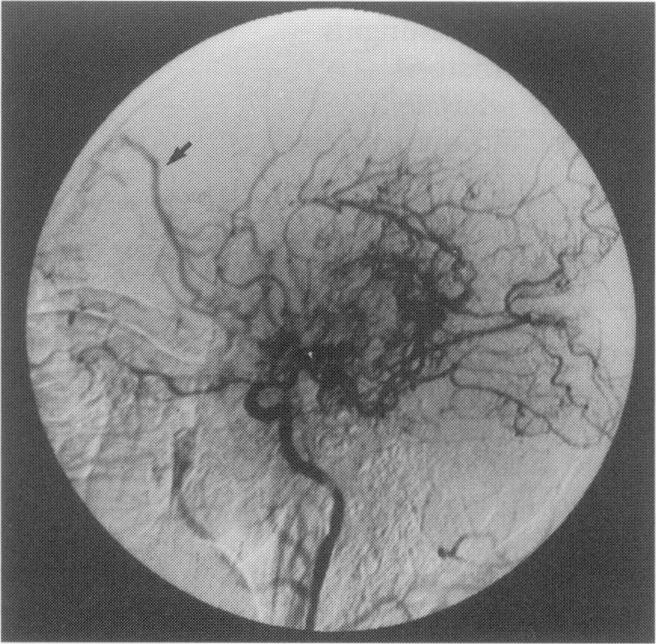

烟雾病

Moyamoya disease.

Moyamoya disease is a rare cerebrovascular condition of uncertain aetiology commonly affecting young persons. The disease is mainly seen in Japanese patients. We report two cases of moyamoya disease in Caucasian women and review the postulated aetiological factors and associated conditions as well as the spectrum of invasive and non-invasive imaging modalities useful in the diagnosis and follow-up of the disease, with particular reference to the developing role of magnetic resonance imaging and angiography.

摘要